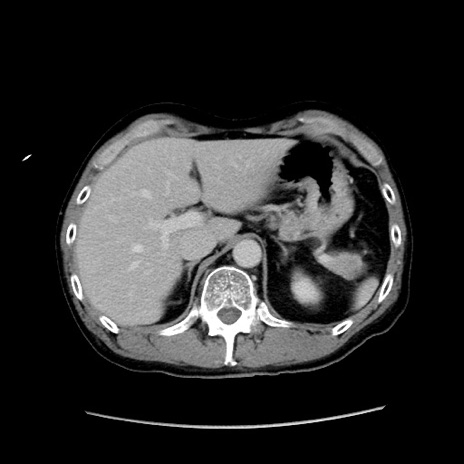

症例37(横断像)

【症例】40歳代 男性

【主訴】腹痛

【現病歴】4時間ほど前に電車に乗車中に臍部上より腹痛出現。徐々に増悪し起立困難となり、救急外来受診。生ものは数日食べていない。今朝お雑煮を食べた。

【身体所見】BT 36.8℃、BP 117/84mmHg、HR 91/min、SpO2 97%、苦悶様、腹部:臍上部広範囲圧痛あり、反跳痛±

【データ】WBC 8100、CRP 0.03